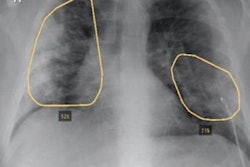

Using over 14,000 ambulatory frontal chest x-rays, the multi-institutional team of researchers trained a multitask deep-learning model to predict comorbidities and then associate these findings with self-reported race/ethnicity recorded in the electronic health record (EHR) software.

In testing on 814 COVID-19 patients, the algorithm yielded an area under the curve (AUC) of 0.99 for predicting patient sex, 0.91 for morbid obesity, 0.88 for congestive heart failure, 0.87 for vascular disease, 0.81 for cardiac arrhythmias, and 0.80 for predicting diabetes with chronic complications.

When modeled with logistic regression analysis, the algorithm's comorbidity scores for chronic obstructive pulmonary disease (COPD) and cardiac arrhythmias were significantly associated with self-reported race/ethnicity (p < 0.05). Overall, the deep learning-based comorbidity model yielded an AUC of 0.65 for predicting self-reported race, compared with 0.61 when using the Medicare Advantage HCC Risk Adjustment Model calculated from EHR data.